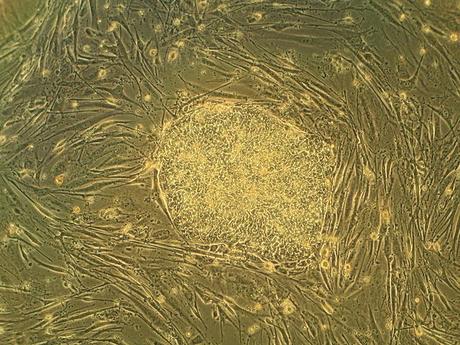

Types of Stem CellsDepending on what stage of development are the individual isolated stem cells they are divided into embryonic and adult stem cells(i.e., somatic stem cells derived from different tissues and organs of the fetus and the adult organism).

induced pluripotent stem cells (iPSCs), which are are produced in a lab environment by

reprogramming adult cells to express embryonic stem cells characteristics.

Embryonic stem cells - isolated from the inner cell mass of the blastocysts (Inner Cell Mass - ICM).

The Blastocyst is formed in the stage of the embryonic development before implantation. It consists of approximately 150 cells, which are divided in the following manner - a layer of cells is arranged on the inside of the blastocyst's cell sphere and is called trofektoderm. They enclose a gap called Blastocoele. Inside the blastocyst a pile of cells is formed - the inner cell mass. It develops the future organism and the cells of the trofektoderm are developing the placenta . ICM cells are pluripotent stem cells. All cell types of germ layers - ecto, meso and endoderm are developed out of them.